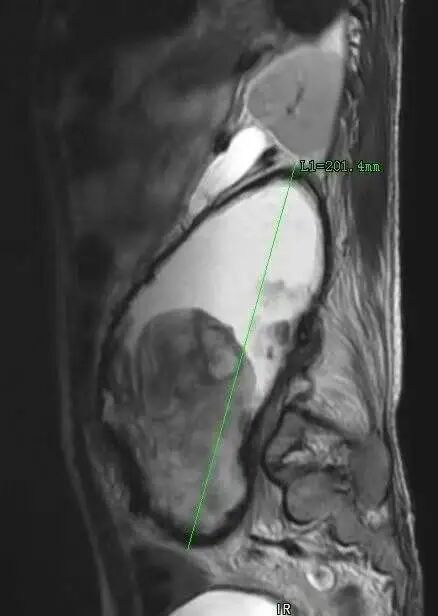

术前影像资料提示:患者左侧腹膜后存在一巨大恶性神经鞘瘤,最大径达20.1厘米。肿瘤已广泛侵犯周围结构,包括同侧髂骨、腰椎以及输尿管。